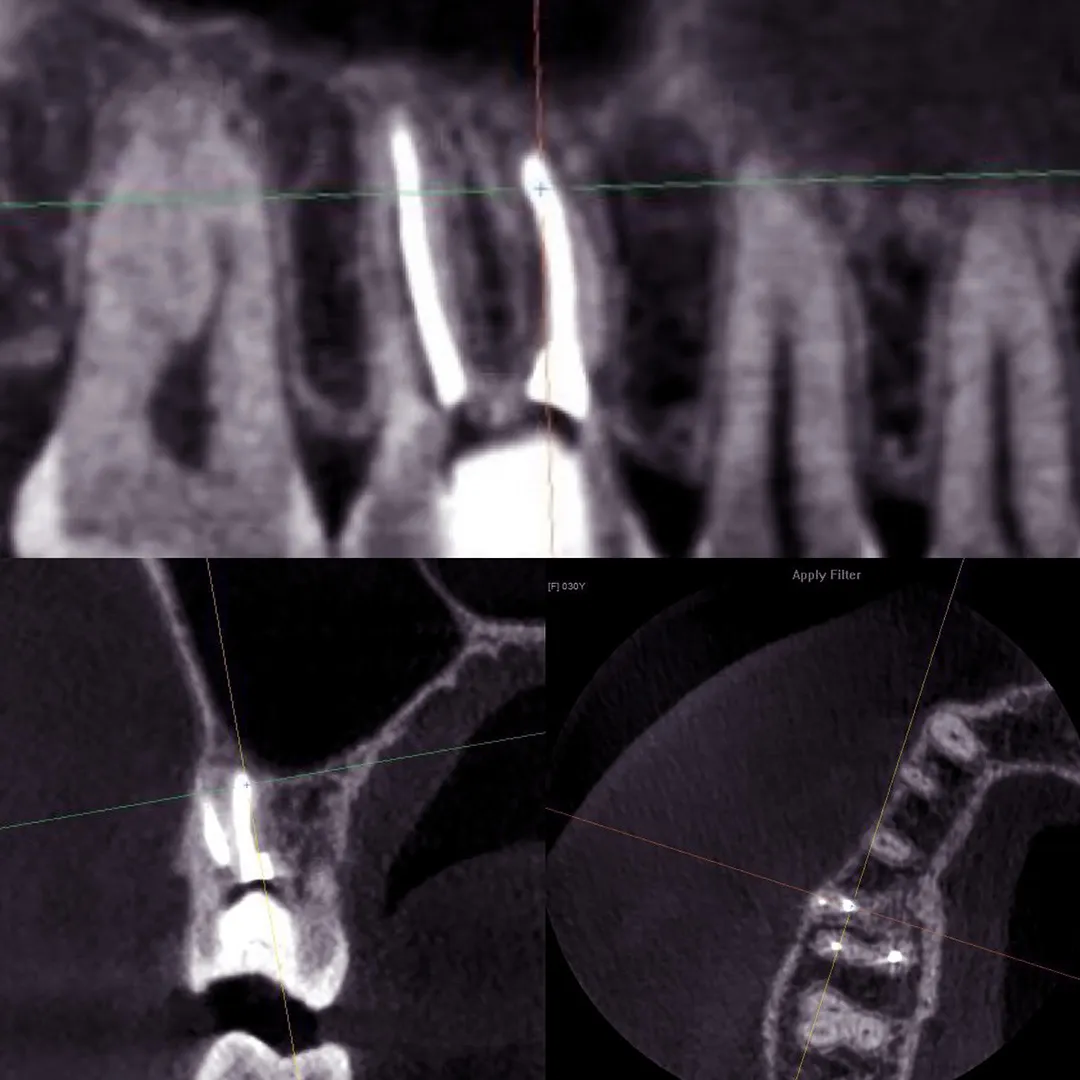

В результате обострения хронического периодонтита и появления ноющих болей проведено пломбирование канала зубаСмотреть работуСрок лечения:2 часаСумма лечения:9 590 руб.